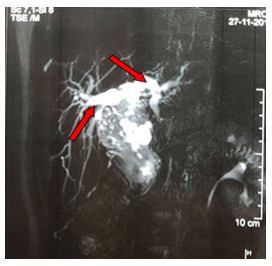

There was a neutrophilic leucocytosis with a high erythrocyte sedimentation rate. The liver function tests were abnormal. Regarding viral markers HBsAg, anti-HAV IgM, anti-HCV IgM were negative except antibodies to herpes simplex virus type 1 (anti-HSV1) IgM were positive (Table 1). In imaging findings, ultrasonogram of the abdomen showed slightly enlarged liver with homogenous echotexture, slightly dilated intrahepatic biliary channels, and fusiform dilatation (3.8 cm × 5.2 cm × 5.8 cm) of the common bile duct (CBD) with soft tissue extending into the distal part of CBD compressing the head of the pancreas, which is suggestive of a choledochal cyst (infected or hemorrhagic – type IVb). An irregular hypoechoic soft tissue mass (5.3 cm × 3.8 cm) near the head of the pancreas and flow within the mass with Resistance Index (RI) = 0.51 is seen in the Doppler study of the portal vein, hepatic veins, and inferior vena cava. Magnetic resonance cholangiopancreatogram (MRCP) revealed gross fusiform dilatation of CBD and common hepatic duct (CHD) producing a sac-like mass 4.3 cm × 2.7 cm in size, slightly dilated intrahepatic biliary channels, and low signal intensity within the dilated CBD and these features suggestive of a choledochal cyst (Type IVb) with sludge and secondary dilatation of intrahepatic biliary radicles (Figure 1).

Figure 1 Results of coronal magnetic resonance cholangiopancreatogram Gross fusiform dilation of the CBD (red arrow) and slightly dilated intrahepatic biliary channel. |

For better evaluation of the biliary channel, we did MRCP that revealed gross fusiform dilatation of the CBD producing sac-like mass and intrahepatic biliary channels slightly dilated, suggestive of choledochal cyst with sludge and secondary dilatation of intrahepatic biliary radicles. Other imaging techniques may be computed tomography (CT) scan or magnetic resonance imaging (MRI). The identification of the solid nature of the tumor by CT scan can sometimes aid differentiation from a choledochal cyst[19]. CT scan and MRI are also helpful to see the extent and staging of the disease[6].